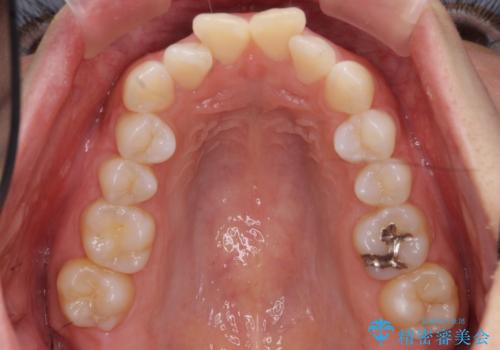

前歯をさげたい 歯を抜かずに マウスピース矯正で治したい

- 上の前歯が出ているとのことで来院。

歯を抜かずに、上の奥歯を後ろにさげつつ上の前歯を小さく少し削る処置を行い前歯の角度を修正しました。

右上下の奥歯もすれ違い咬合も、治療で改善しています。

下の前歯が生まれつき3本でしたので上下の正中は合わない仕上がりとなります。